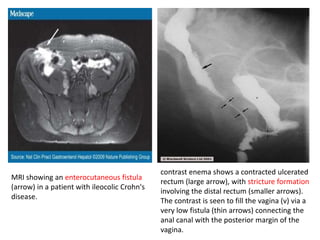

MRI showing an enterocutaneous fistula

(arrow) in a patient with ileocolic Crohn's

disease.

contrast enema shows a contracted ulcerated

rectum (large arrow), with stricture formation

involving the distal rectum (smaller arrows).

The contrast is seen to fill the vagina (v) via a

very low fistula (thin arrows) connecting the

anal canal with the posterior margin of the

vagina.